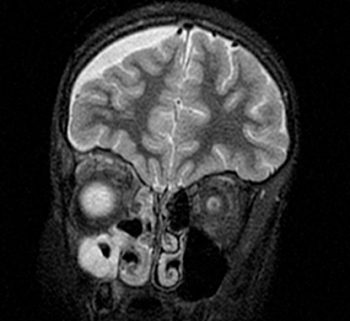

Caso 2. Niña de 10 años que ingresa por un cuadro de celulitis orbitaria acompañada de cefalea y vómitos. Se realiza una prueba de imagen que objetiva una colección intraorbitaria derecha y pansinusitis (Fig. 3). Se realiza drenaje del absceso orbitario e ingresa con tratamiento intravenoso con amoxicilina-clavulánico y ciprofloxacino ante el aislamiento en el exudado del absceso ocular de Streptococcus intermedius y en hemocultivo, de Moraxella osloensis. Ante la ausencia de mejoría clínica al cuarto día posquirúrgico, se decide realizar nueva imagen radiológica, que muestra la aparición de un empiema subdural frontal derecho (Fig. 4). Se sustituye amoxicilina-clavulánico por cefotaxima y se añade dexametasona al tratamiento. Se realiza craneotomía frontal derecha para drenar el empiema. En las muestras recogidas se aísla Streptococcus intermedius y Parvimonas micra, motivo por el que se asocia al tratamiento metronidazol intravenoso. La evolución, clínica y radiológica, es favorable tras seis semanas de tratamiento antibiótico intravenoso, y permanece asintomática al alta.

| Figura 4. Absceso en región superomedial de la órbita derecha y empiema subdural derecho. TC de cráneo: empiema subdural frontal-parietal-temporal derecho con grosor máximo de 9 mm, que produce discreto efecto masa sin desplazamiento de la línea media; colección abscesificada en región superomedial de la órbita derecha, que ha aumentado de tamaño respecto a estudio previo; sinusitis derecha aguda |